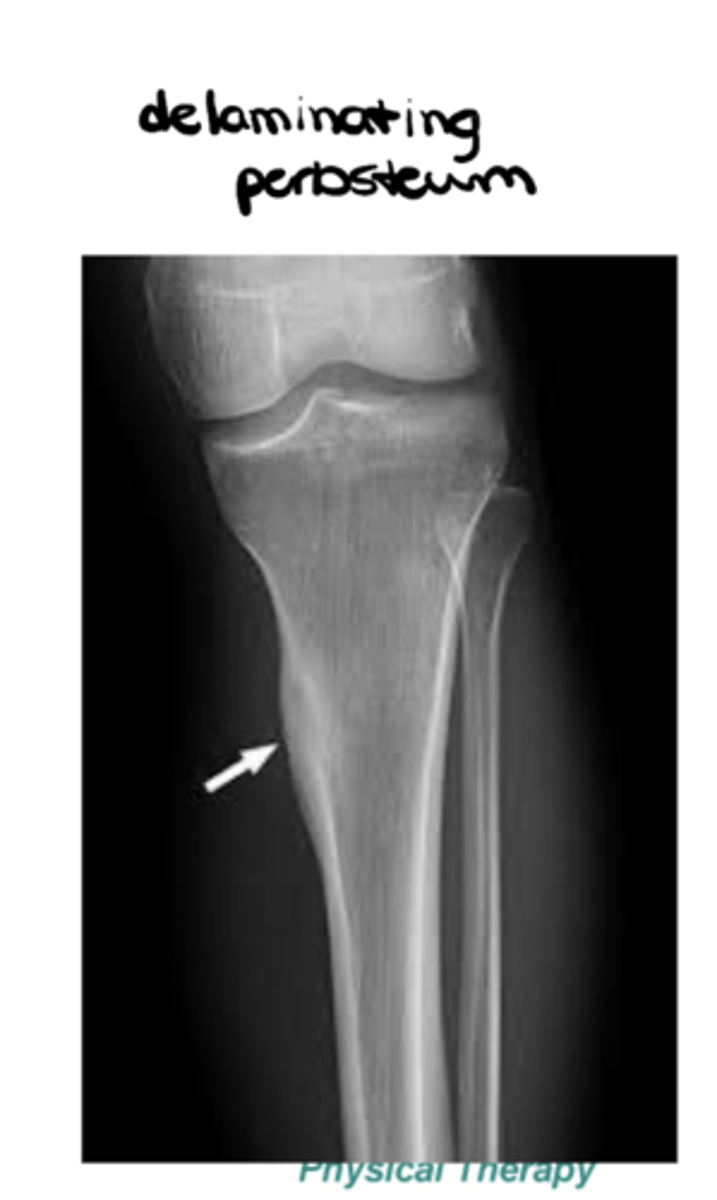

List the sub-components of (S) soft tissues: periosteum (sheath outside of cortical bone that sits on top of it)

- Solid

- Laminated

- Sunburst

- Codman's triangle